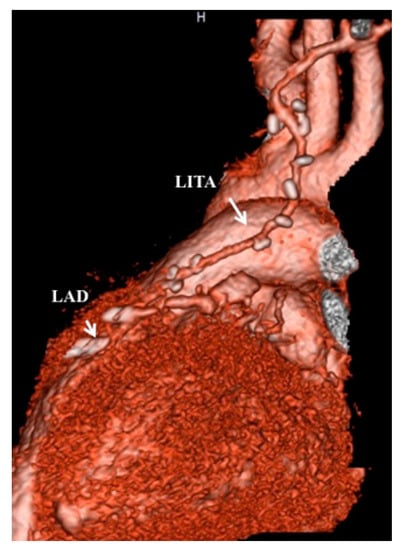

- Tsuda, E.; Kitamura, S.; Kimura, K.; Kobayashi, J.; Miyazaki, S.; Echigo, S.; Yagihara, T. Long-term patency of internal thoracic artery grafts for coronary artery stenosis due to Kawasaki disease: Comparison of early with recent results in small children. Am. Heart J. 2007, 153, 995–1000. [Google Scholar] [CrossRef] [PubMed]

- Kitamura, S.; Seki, T.; Kawachi, K.; Morita, R.; Kawata, T.; Mizuguchi, K.; Kobayashi, S.; Fukutomi, M.; Nishii, T.; Kobayashi, H.; et al. Excellent patency and growth potential of internal mammary artery grafts in pediatric coronary bypass surgery: New evidence for a “live” conduit. Circulation 1989, 78, I129–I139. [Google Scholar]